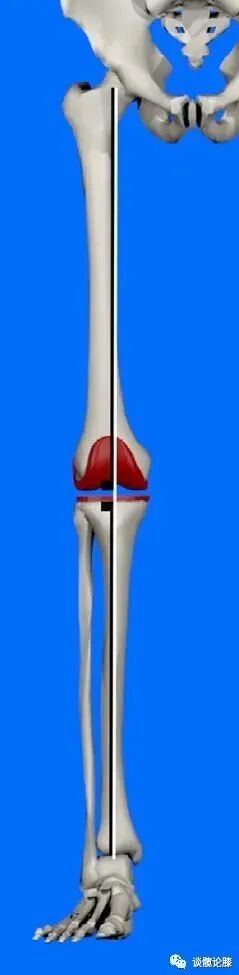

机械对线技术【Mechanical Alignment (MA) technique】 MA技术,即股骨远端和胫骨近端截骨面均垂直机械轴线,使下肢轴线与关节线垂直。